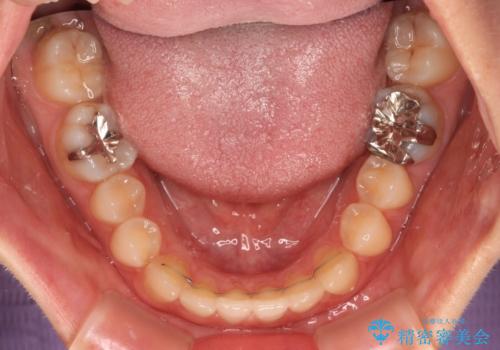

前歯のクロスバイト インビザラインによる矯正治療

- 前歯のクロスバイトとデコボコを気にして来院された患者様です。

骨格的に下顎前突傾向であるため、自己管理が煩わしくないようであれば、インビザラインによる矯正治療がお勧めとなります。

インビザラインを用い、下顎歯列を後方に移動させながら全市の被蓋を改善し、歯並びを整えていくこととしました。

途中マウスピースが使用できず、来院されない期間があり、治療期間は長くかかりましたが、無事に治療を終えることができました。